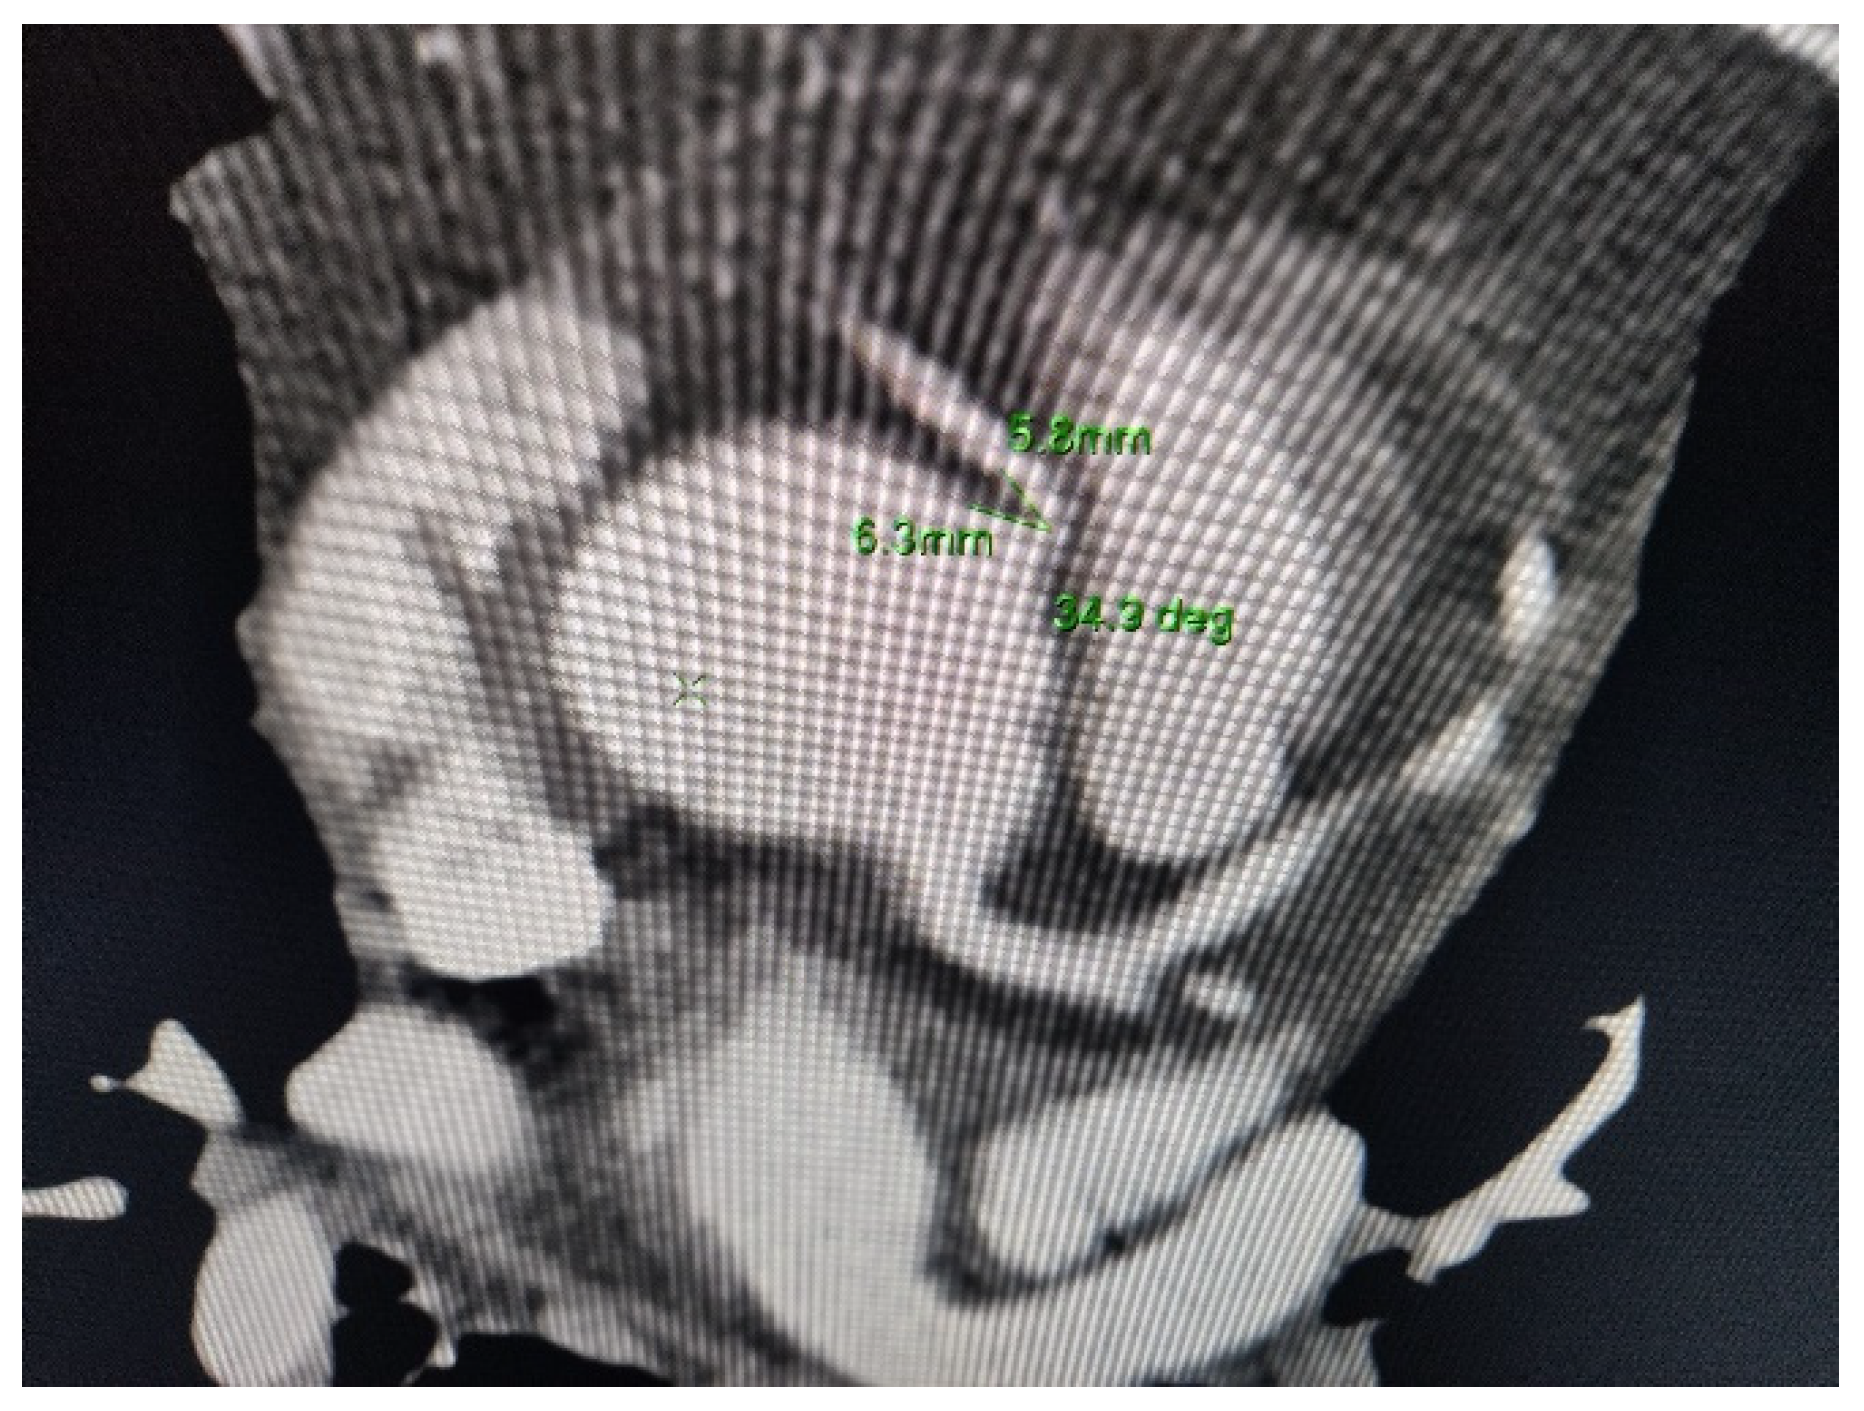

A Curve Maybe to Narrow: Description of an Anomalous Course of the Right Coronary Artery

Pastorini, G.; Bertone, E.; Talenti, A.; Feola, M. A Curve Maybe to Narrow: Description of an Anomalous Course of the Right Coronary Artery. Diseases 2021, 9, 62. https://doi.org/10.3390/diseases9030062